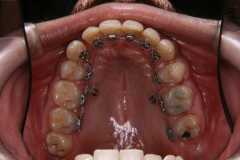

上下の歯の裏側にブラケット装置をつけている治療例

*新宿の常盤矯正歯科医院より写真提供

見た目には歯列矯正をしているようには見えませんが、歯の裏側に矯正装置のブラケットが付いています。